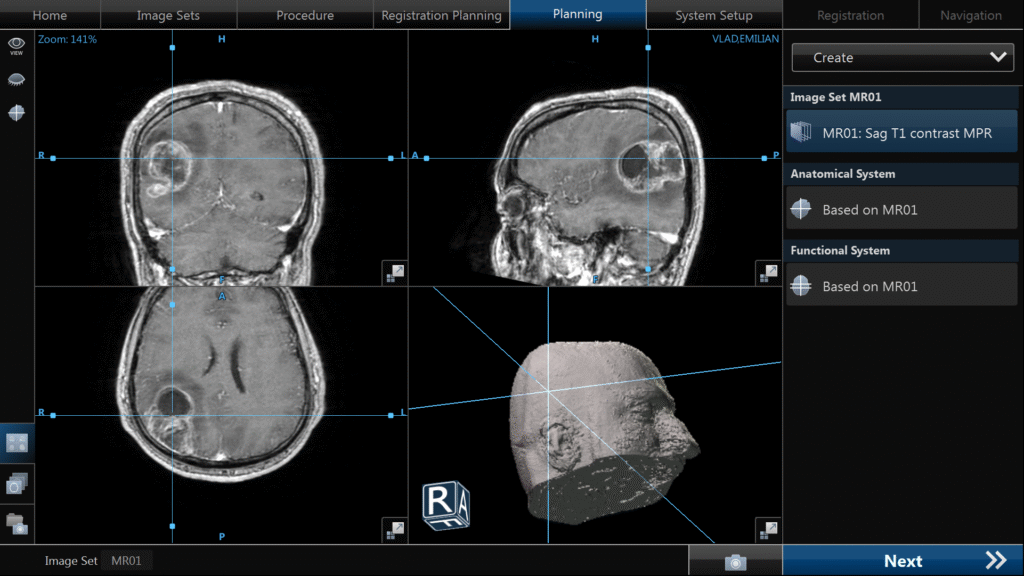

Chirurgia – rol central, dar nu curativ

Chirurgia reprezintă primul pas terapeutic și unul dintre cei mai importanți factori prognostici modificabili.

Conceptul actual este cel de rezecție maximală sigură, care implică:

- îndepărtarea cât mai extinsă a tumorii vizibile

- conservarea funcțiilor neurologice esențiale

Extensia rezecției este direct corelată cu supraviețuirea, însă beneficiul se pierde dacă este însoțit de deficit neurologic semnificativ.

Tehnologiile moderne au crescut semnificativ siguranța:

- fluorescența 5-ALA permite identificarea țesutului tumoral activ

- neuronavigația oferă orientare spațială precisă

- monitorizarea neurofiziologică protejează funcțiile motorii

- chirurgia awake permite cartografierea limbajului și a funcțiilor cognitive

În practică, fiecare intervenție este o negociere fină între radicalitate și funcție.

- Obligatoriu RMN cerebral cu contrast și protocol 3D pentru neuronavigație.

Etapa 2 – Intervenția chirurgicală

- Cât mai repede de la momentul diagnosticului.

- Scop: îndepărtarea completă a tumorii fără afectarea funcțiilor neurologice.

- Mijloace: microscop operator, neuronavigație, monitorizare neurofiziologică intraoperatorie (awake surgery), fluorescență 5-ALA.

- Intervenție minim-invazivă, spitalizare minimă (3-5 zile), recuperare rapidă.

- Pacienții inoperabili – biopsie ghidată prin neuronavigație.